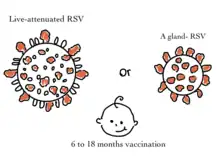

Vaccines

There is interest and research in RSV vaccine discovery, given the virus's disease burden and the lack of disease-specific therapies. Vaccine development has faced obstacles that have blocked its progress. Among these are infant-specific factors, such as the immature infant immune system and the presence of maternal antibodies, which make infantile immunization difficult.[3]

RSV infection is widespread in early childhood, contributing significantly to global disease burden. The association between severe childhood infections and subsequent respiratory issues is not fully understood, particularly the suggested link between bronchiolitis, recurrent infantile wheeze, and childhood asthma. Unlike other vaccine-preventable respiratory pathogens, RSV has proven challenging for vaccine development. Ongoing efforts focus on creating vaccines that confer durable protection, with field trials eagerly anticipated. Currently, supportive care is the mainstay for treating RSV disease, as effective vaccines and antiviral drugs are awaited. The introduction of antivirals and vaccines, coupled with advanced diagnostic techniques, holds promise for reducing RSV's global impact in the coming years. These interventions may alter infection dynamics and weaken RSV's hold on communities worldwide.[3]

Potential vaccines being researched fall into five broad categories: live-attenuated, protein subunit, vector-based, virus particle subunit, and messenger RNA. Each targets different immune responses, and thus may be better suited to prevent disease in different at-risk groups. Live-attenuated vaccines have shown some success in RSV-naive infants. Other vaccine candidates hope to target vulnerable populations across the lifespan, including pregnant women and the elderly.[37][3]